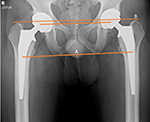

| Bilateral total hip arthroplasty (THA) |

38 year old man with bilateral THA for advanced osteoarthritis. The distances from a line (C) between the centers of the femoral heads to a line running tangential to the ischial tuberosities (A) should be equal on each side, and the distances between the centers of the femoral heads to a line (B) running tangential to the tops of the greater trochanters should be equal on each side. Lines A, B, C should be parallel. |

38 year old man with bilateral THA for advanced osteoarthritis. The distances from the centers of the femoral heads on each side to the tops of the acetabular tear drops should be equal. |